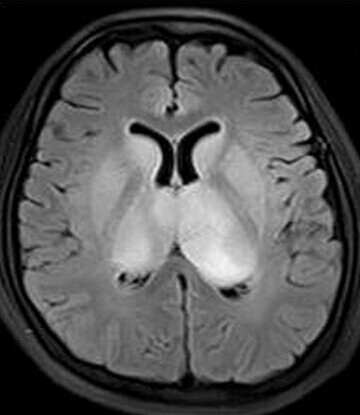

患者:女,23岁,主因嗜睡、言语不利三个月,四肢无力、吞咽障碍3个月入院。

查体:嗜睡,构音障碍,双侧掌颌反射阳性,四肢肌力Ⅳ级

【正确答案】D 大脑胶质瘤病

大脑胶质瘤病的特征性影像学表现是:

(1)肿瘤常累及2-3个脑叶,白质改变为主,占位效应不明显或轻度占位效应;

(2)病变区大脑结构相对保留;

(3)增强后多无强化。

双侧丘脑基底节对称性长T1WI长T2WI异常信号,flair高信号,脑组织清淡肿胀,1.颞叶未见异常,一般脑炎易颞叶受累,首先不考虑炎症;2.静脉窦血栓,双侧应该双侧髓静脉会合后的大脑大静脉,如果血栓,硬牵连到部分胼胝体,似乎看到大脑大静脉血管流空,不像血栓形成;3.肿瘤更不像,肿瘤生长不会跨过白质只生长在灰质;4.代谢性疾病,大多对称性,太多,没有特异性,很难说出是那种。首先考虑代谢疾病